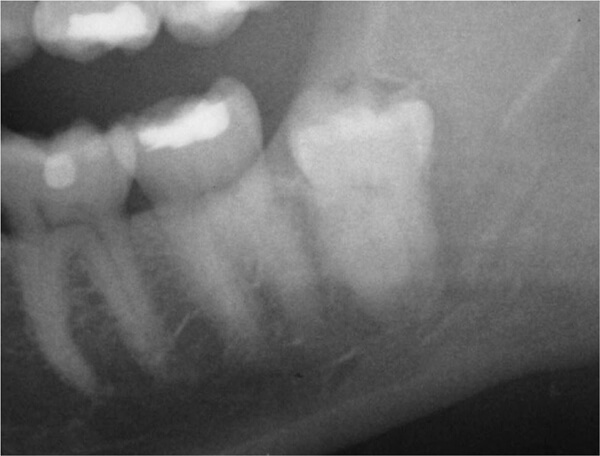

①上顎埋伏智歯

上顎の智歯(親知らず)が骨に埋まっている状態。(上顎洞近接)